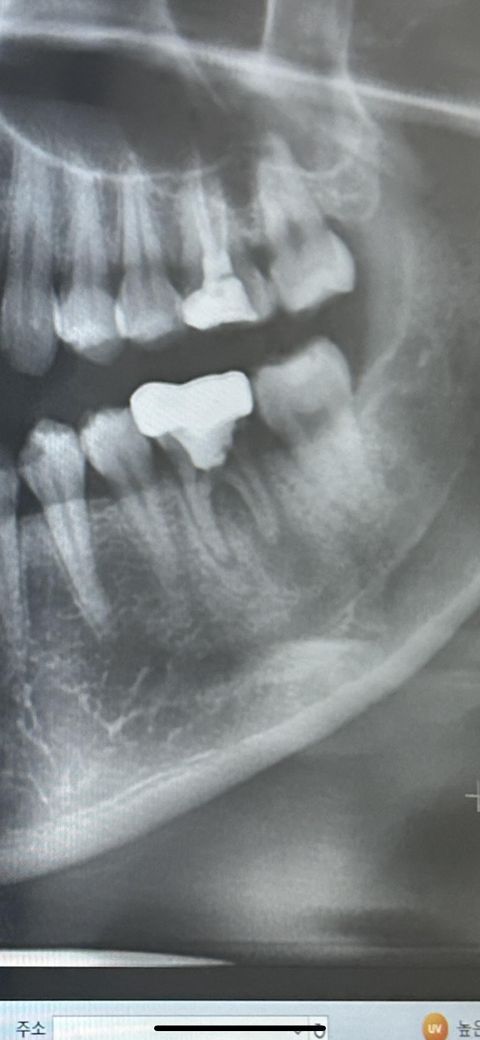

어금니 염증으로 통증이 있습니다 꼭 발치해야 할까요?

통증이 있고 염증이 심한상태라고 발치 후 임플란트 권장하였습니다 최대한 자연치아를 꼭 살리고 싶은데 도저히 가망히 없는지 궁금합니다

염증이 너무 많이 진행된 경우에는 치아를 살리기 힘든 경우가 많으며 위의 치아도 살리기 어려워 보입니다.

• 사진으로 봤을 경우에는 씨앗 뿌리에 뒤쪽으로 해서 깊은 병소가 보입니다 시야가 파절되었을 때 해당 사진과 같은 증상이 나타나는 경우가 많이 있습니다.

치아가 파절되어서 생긴 증상이라면 치아를 발치해 줘야 할 수도 있습니다 자세한 확인을 위해서 치과에서 진료를 받아 보세요.

• 염증이 아주 심한 상태는 맞습니다 염증이 잇몸뼈까지 많이 퍼져서 잇몸뼈를 녹인 상태이고요 이 상태에서 신경치료 및 잇몸치료를 진행한다 쳐도 치아자체를 오래 유지하지 못할수도 있습니다

신경치료하고 잇몸치료하는 것도 험난한 과정이고 여러번 내원하고 하느라 불편할 수 있는데 그렇게 해도 치아를 살리지 못하게 될 가능성이 높으므로 그럴꺼면 그냥 빼고 임플란트를 하자고 하신 겁니다.